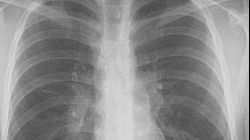

Oamenii de ştiinţă vor putea să detecteze primele semne ale cancerului pulmonar cu ajutorul unui test respirator care este "ieftin şi simplu", informează dailymail.co.uk.

Cercetătorii de la Facultatea de medicină din cadrul Universităţii Louisville din Statele Unite au descoperit o metodă eficientă pentru a distinge cu acurateţe între bolile pulmonare benigne şi cancerul pulmonar aflat în stadii incipiente.

Testul conceput de cercetătorii americani oferă acelaşi nivel de acurateţe ca actuala tehnică - tomografie cu emisie de pozitroni (PET) -, dar cu o specificitate aproape de două ori mai mare.

Noul test ar putea accelera începerea tratamentului pentru pacienţii diagnosticaţi cu cancer pulmonar în stadii incipiente şi ar reprezenta o povară mai uşoară - fizică şi financiară - pentru pacienţi.

Cercetătorii au utilizat microcipuri din silicon pentru a colecta mostre respiratorii de la 88 persoane sănătoase, 107 pacienţi cu cancer pulmonar, 40 de persoane cu boli pulmonare benigne şi de la şapte pacienţi cu cancer pulmonar metastazat.

Studiile precedente au identificat în mostrele respiratorii patru substanţe specifice, denumite "compuşi carbonilici", care sunt "markeri superiori ai cancerului" (ECM), capabili să facă distincţia între pacienţii cu cancer pulmonar şi pacienţii cu maladii pulmonare benigne.

Acurateţea şi specificitatea testelor respiratorii depind de creşterile înregistrate de concentraţiile acestor ECM.

De exemplu, detectarea a trei din cei patru ECM cunoscuţi echivalează cu diagnosticarea corectă a cancerului pulmonar în 95% din cazuri.

În ceea ce priveşte diferenţierea stadiilor incipiente de cancer pulmonar de bolile pulmonare benigne, testele respiratorii şi tehnica PET au prezentat rezultate comparabile - 82,8% respectiv 90,3%.

Totuşi, testele respiratorii au generat o specificitate mult mai mare decât metoda PET - 75% faţă de 38,7% - în ceea ce priveşte diferenţierea bolilor benigne, ceea ce înseamnă că ele au o acurateţe mult mai mare în identificarea pacienţilor care nu au cancer.

Acest test îi va ajuta foarte mult pe pacienţii cu boli benigne, întrucât realizarea unui test respirator în locul unei analize PET îi va ajuta să evite o serie de proceduri medicale - biopsie - care nu le sunt necesare.